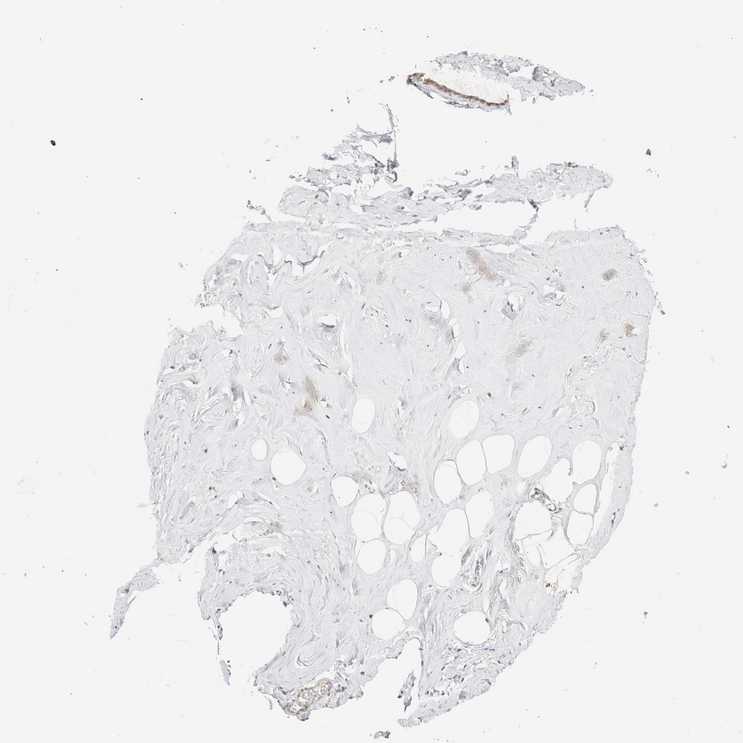

SOFT TISSUE 1 - Antibody stainingi

Antibody staining in the annotated cell types in the current human tissue is reported as not detected, low, medium, or high, based on conventional immunohistochemistry profiling in selected tissues. This score is based on the combination of the staining intensity and fraction of stained cells.

Each image is clickable and will lead to virtual microscopy that enables deeper exploration of all samples and also displays staining intensity scores, fraction scores and subcellular localization as well as patient and tissue information for each sample.

Antibody HPA024204

Chondrocytes Not detected

Fibroblasts Not detected